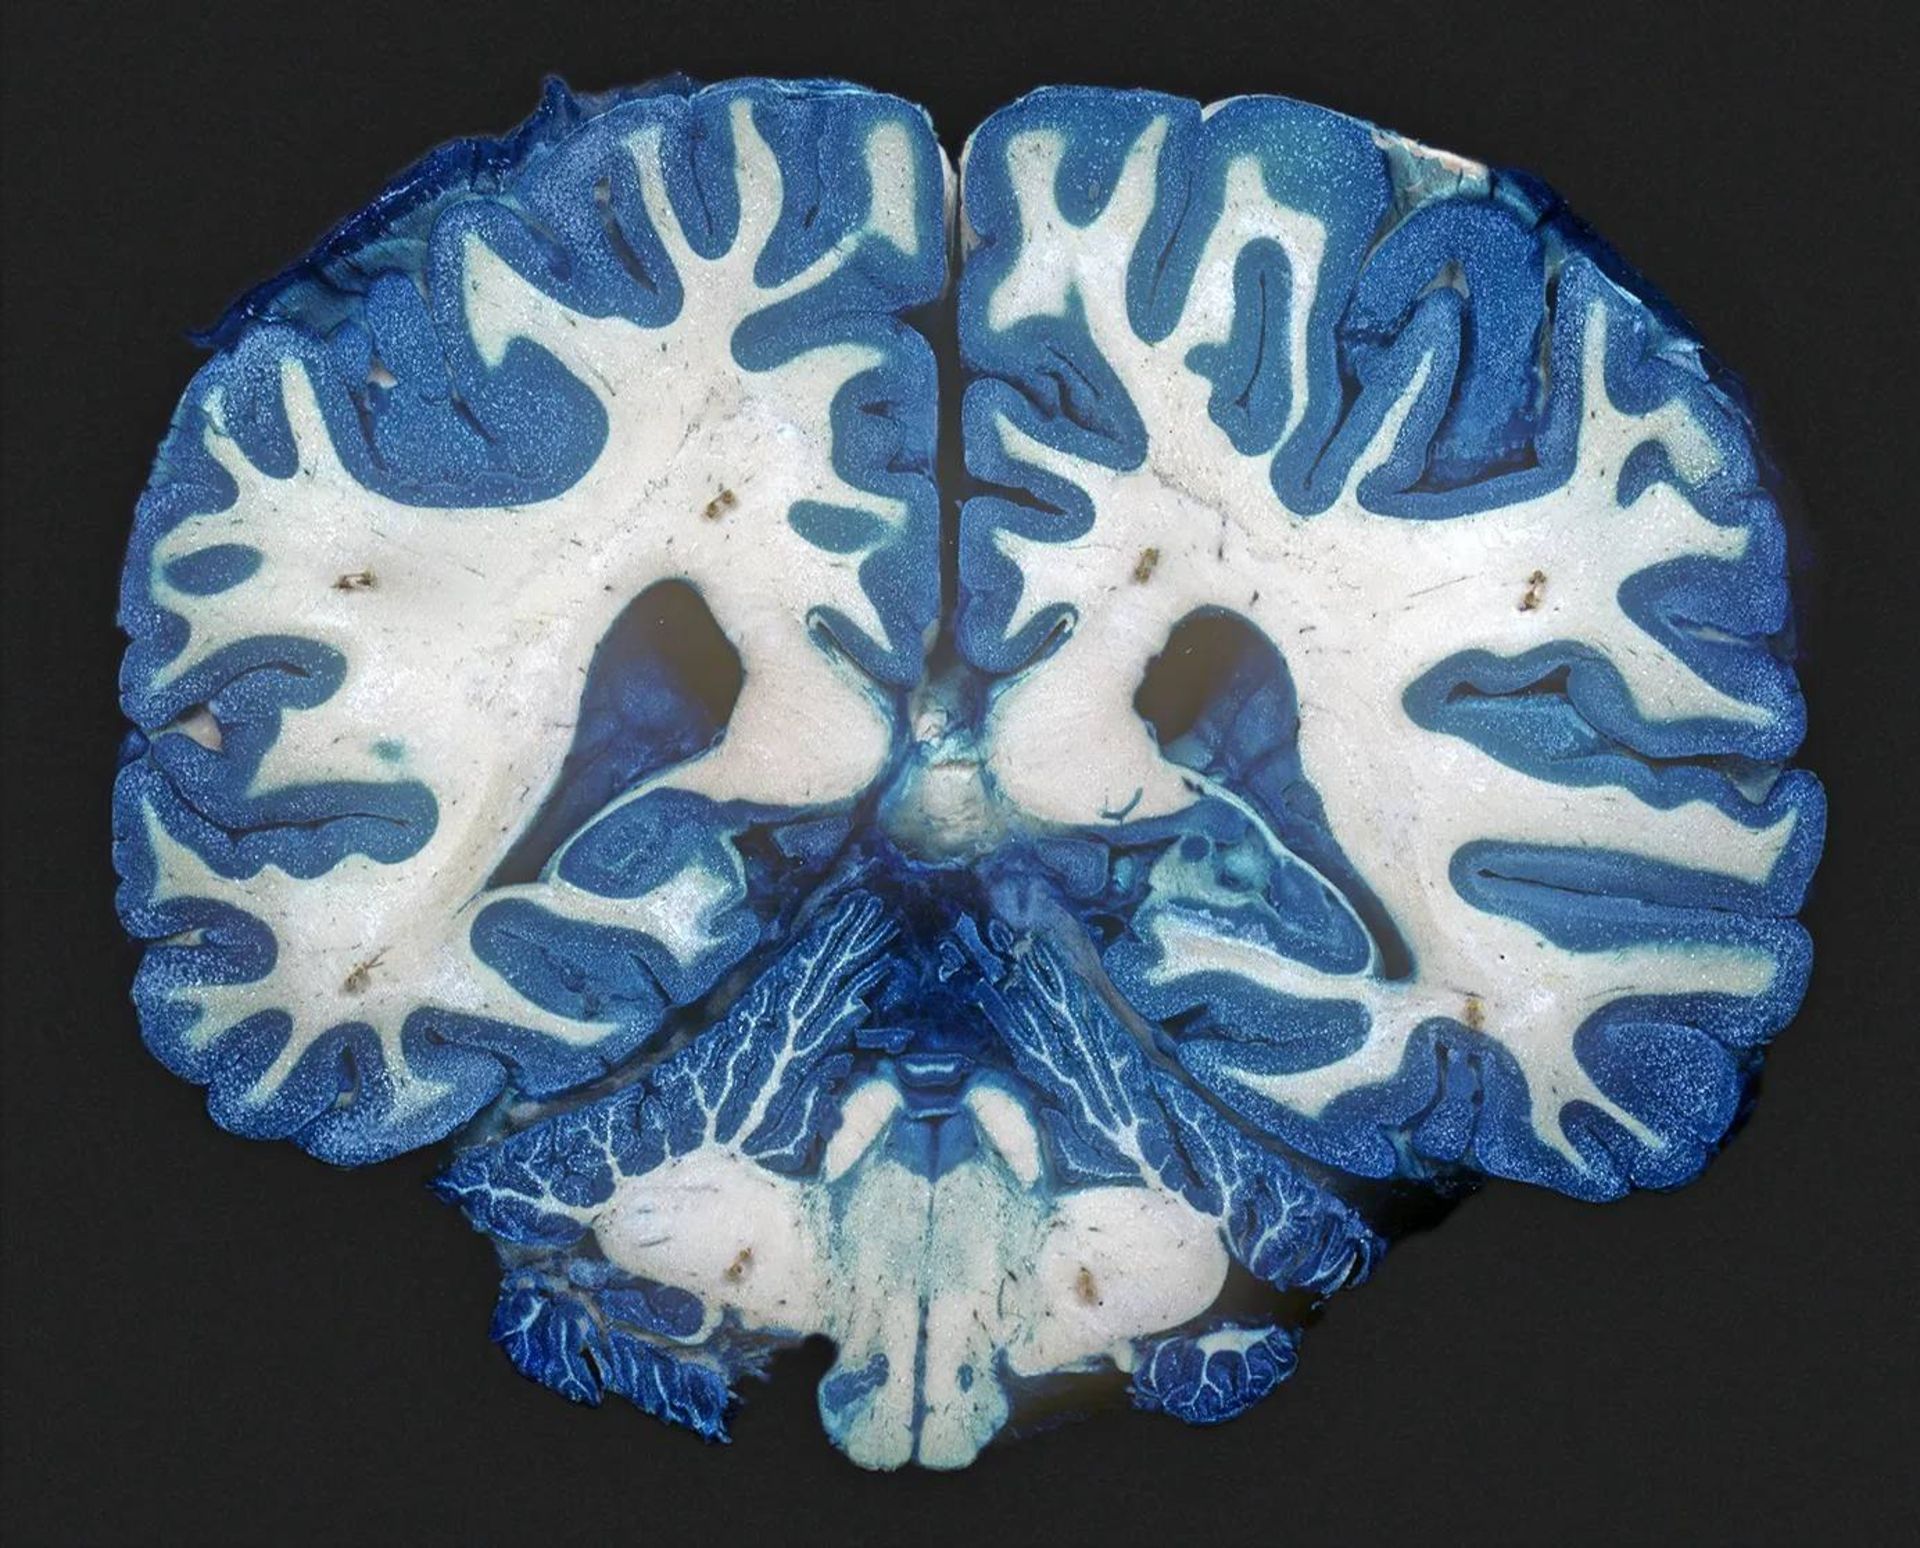

مغز

پژوهش‌ها نشان می‌دهد در مغز افراد مبتلا به افسردگی مزمن، ماده سفید که سرشار از رشته‌های عصبی است، اتصالات کمتری دارد. اگرچه علت این تفاوت نامشخص است.

در کنفرانسی که اخیرا برگزار شد، تیمی به سرپرستی جاناتان رپل، پژوهشگر روانپزشکی دانشگاه گوته آلمان توضیح داد که آن‌ها با اسکن مغز داوطلبان دچار افسردگی حاد دریافتند که مغز افراد مبتلا به افسردگی ازنظر ساختار با مغز گروه غیرافسرده تفاوت دارد. برای مثال، افراد دچار افسردگی دارای اتصالات کمتری درون ماده سفید مغزشان بودند. (اگرچه از نظر ماده سفید مغز آستانه‌ای وجود ندارد که تعریف‌کننده سلامت روان ضعیف باشد: رپل خاطرنشان می‌کند که با اسکن مغز فرد نمی‌توانید افسردگی را تشخیص دهید).